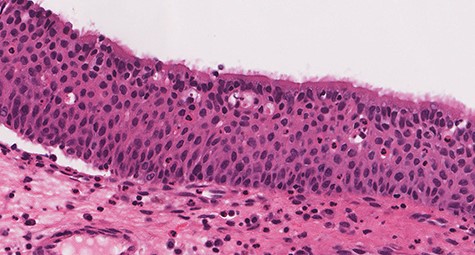

Histologic sections show an endophytic (inverted) pattern that grows downward into the underlying stroma (Fig. 4). The epithelium consists of hyperplastic squamous epithelium (Fig. 5) and ciliated columnar cells admixed with scattered mucocyets (goblet cells) (Fig. 6). The cells have a bland appearance and uniform small nuclei. No cytologic atypia, increased mitotic activity or necrosis seen. Mixed inflammatory cells are dispersed within the epithelium and stroma.

![Section of IP (hematoxylin and eosin [H&E] stain; ×29).](https://oupdevcdn.silverchair-staging.com/oup/backfile/Content_public/Journal/jscr/2020/8/10.1093_jscr_rjaa180/1/m_rjaa180f4.jpeg?Expires=1770025183&Signature=GzL9MbKsK6--L8BpaFn8KbPB1vTqJXt8JLmBi40Al~aNVXHBcE3WBdMSNWceP4etM3oRO68BydJcpTLlYl5cgweZ8DEIzjSbjtdjLGkWsf71cqBx8tP3XyTG5ovxrAyY~3pLYTY4PaM40fvVDaQlr9WMcDpaNJH0~9XEoPBGlgiv3lkp~t-yXGUUHt5RTCWK3fn6LL63As6R31I8tk7x-SubFeXlspgLcssufoygDcYrzVLJDLTKUVrZzPV~B~ehrqSpeZn-nFV2aF17tnDG9fhSNfRJPT6uXqs~0dIEvuoQdXQTt1TmLV1gfn0lHYzI585I4MXrJiuEc4H~HSNbHA__&Key-Pair-Id=APKAIYYTVHKX7JZB5EAA)